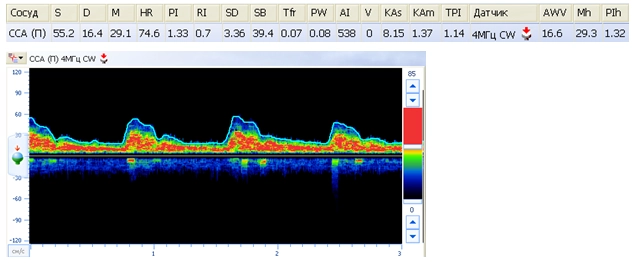

В качестве примера на рис. 3 приведено доплерографическое исследование сосудов головного мозга одного из пациентов.